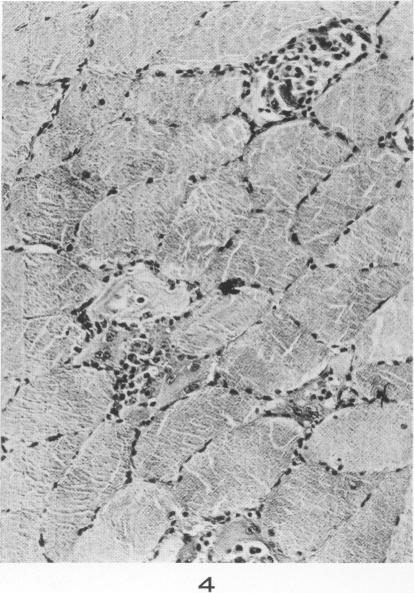

Lesions of skeletal muscle in leptospirosis; review of reports and an experimental study.

Am J Pathol. 1955 May-Jun;31(3):501-19.